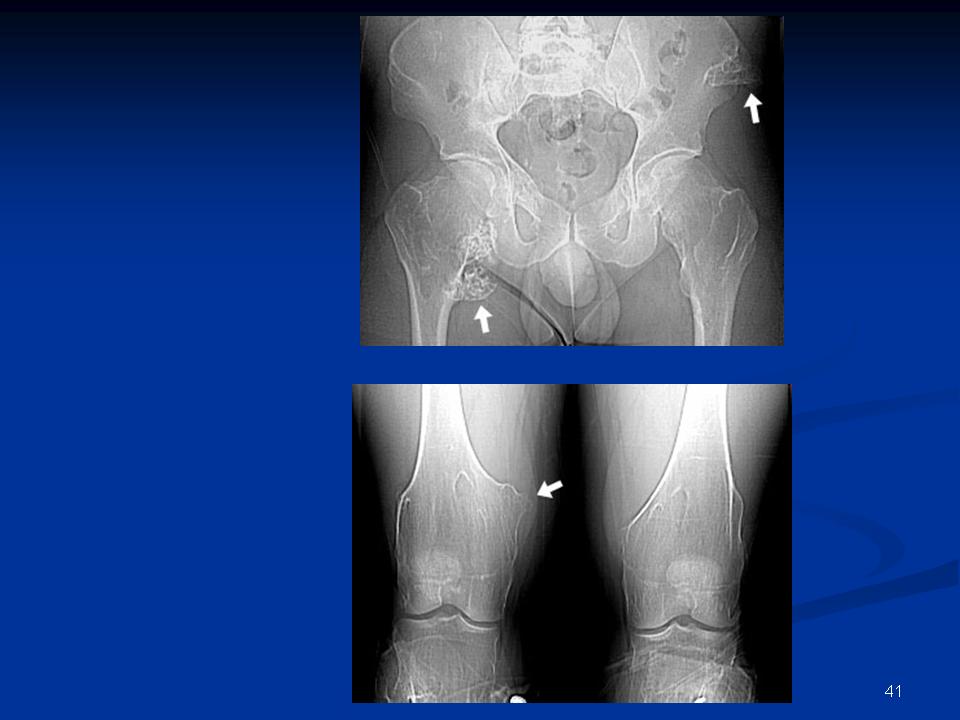

Рентгеновские снимки доброкачественных опухолей костей